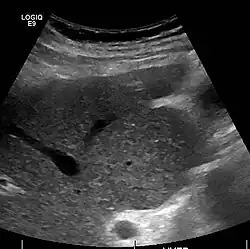

Caudate lobe hypertrophy on ultrasound due to cirrhosis

Hepatofugal (non-forward) flow in portal vein

Imaging

Ultrasound is routinely used in the evaluation of cirrhosis.[45] It may show a small and shrunken liver in advanced disease. On ultrasound, there is increased echogenicity with irregular appearing areas.[64] Other suggestive findings are an enlarged caudate lobe, liver surface nodularity[65] widening of the fissures and enlargement of the spleen.[66] An enlarged spleen, which normally measures less than 11–12 cm (4.3–4.7 in) in adults, may suggest underlying portal hypertension.[67] Ultrasound may also screen for hepatocellular carcinoma and portal hypertension.[45] This is done by assessing flow in the hepatic vein.[68] An increased portal vein pulsatility may be seen. However, this may be a sign of elevated right atrial pressure.[69] Portal vein pulsatility is usually measured by a pulsatility index (PI).[68] A number above a certain value indicates cirrhosis (see table below).